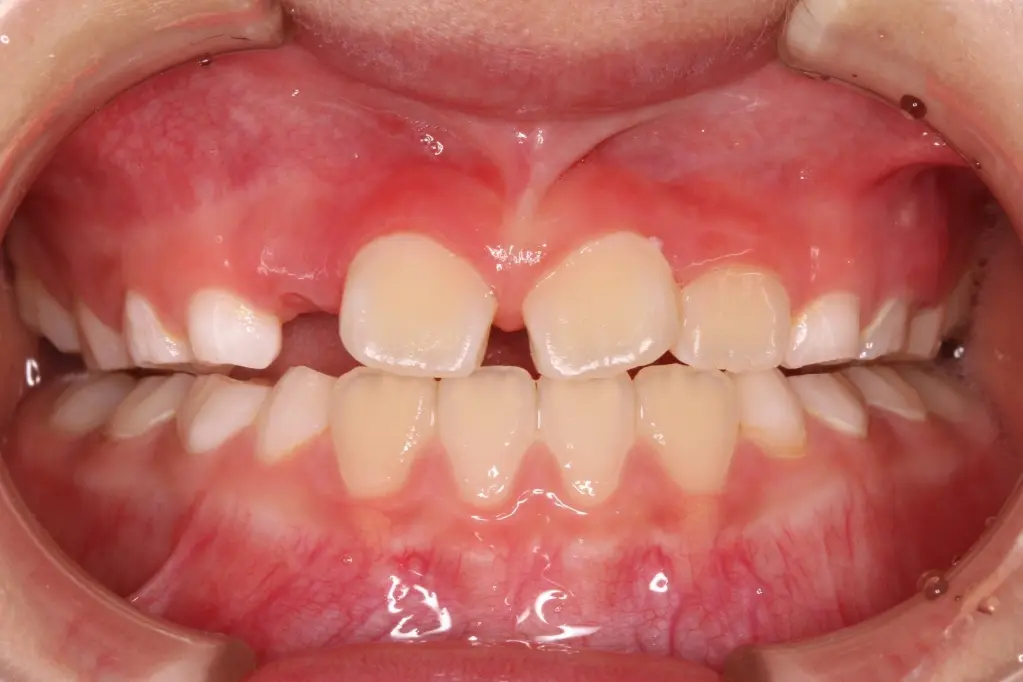

反対咬合(受け口)の6才のお子さんが、プレオルソによって咬み合わせが改善した例です。

治療前(Before) 治療前の状態

【治療開始時】

6才、下の前歯が上の前歯より前に出ている「反対咬合」の状態。骨格性の反対咬合に移行する可能性などを考え、この時点から治療を開始しました。